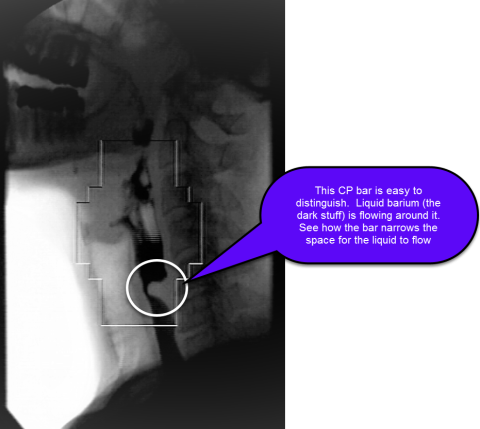

Diagnosis of the CP bar is made with fluoroscopic swallow study of the pharynx and proximal esophagus, typically in the lateral view. The bar appears as an indentation on the barium column at the posterior aspect of the esophagus between the C3 and C6 vertebral levels (see figure).